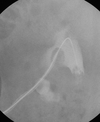

This picture shows the “Ball on tree” appearance of Medullary type RPN

https://www.ctisus.com/responsive/learning/exhibit/genitourinary/311982